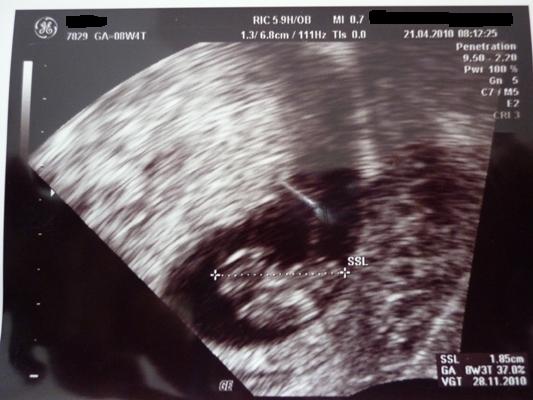

@Leo kann verstehen das du dir Sorgen machst aber die sind bestimmt unbegründet. Deine Unterleibschmerzen kommen bestimmt davon das sich deine Mutterbänder dehnen. Schließlich braucht dein Krümelchen Platz. Morgen ist ja auch schon wieder Krümel-TV. Wirst sehen alles ist in Ordnung.